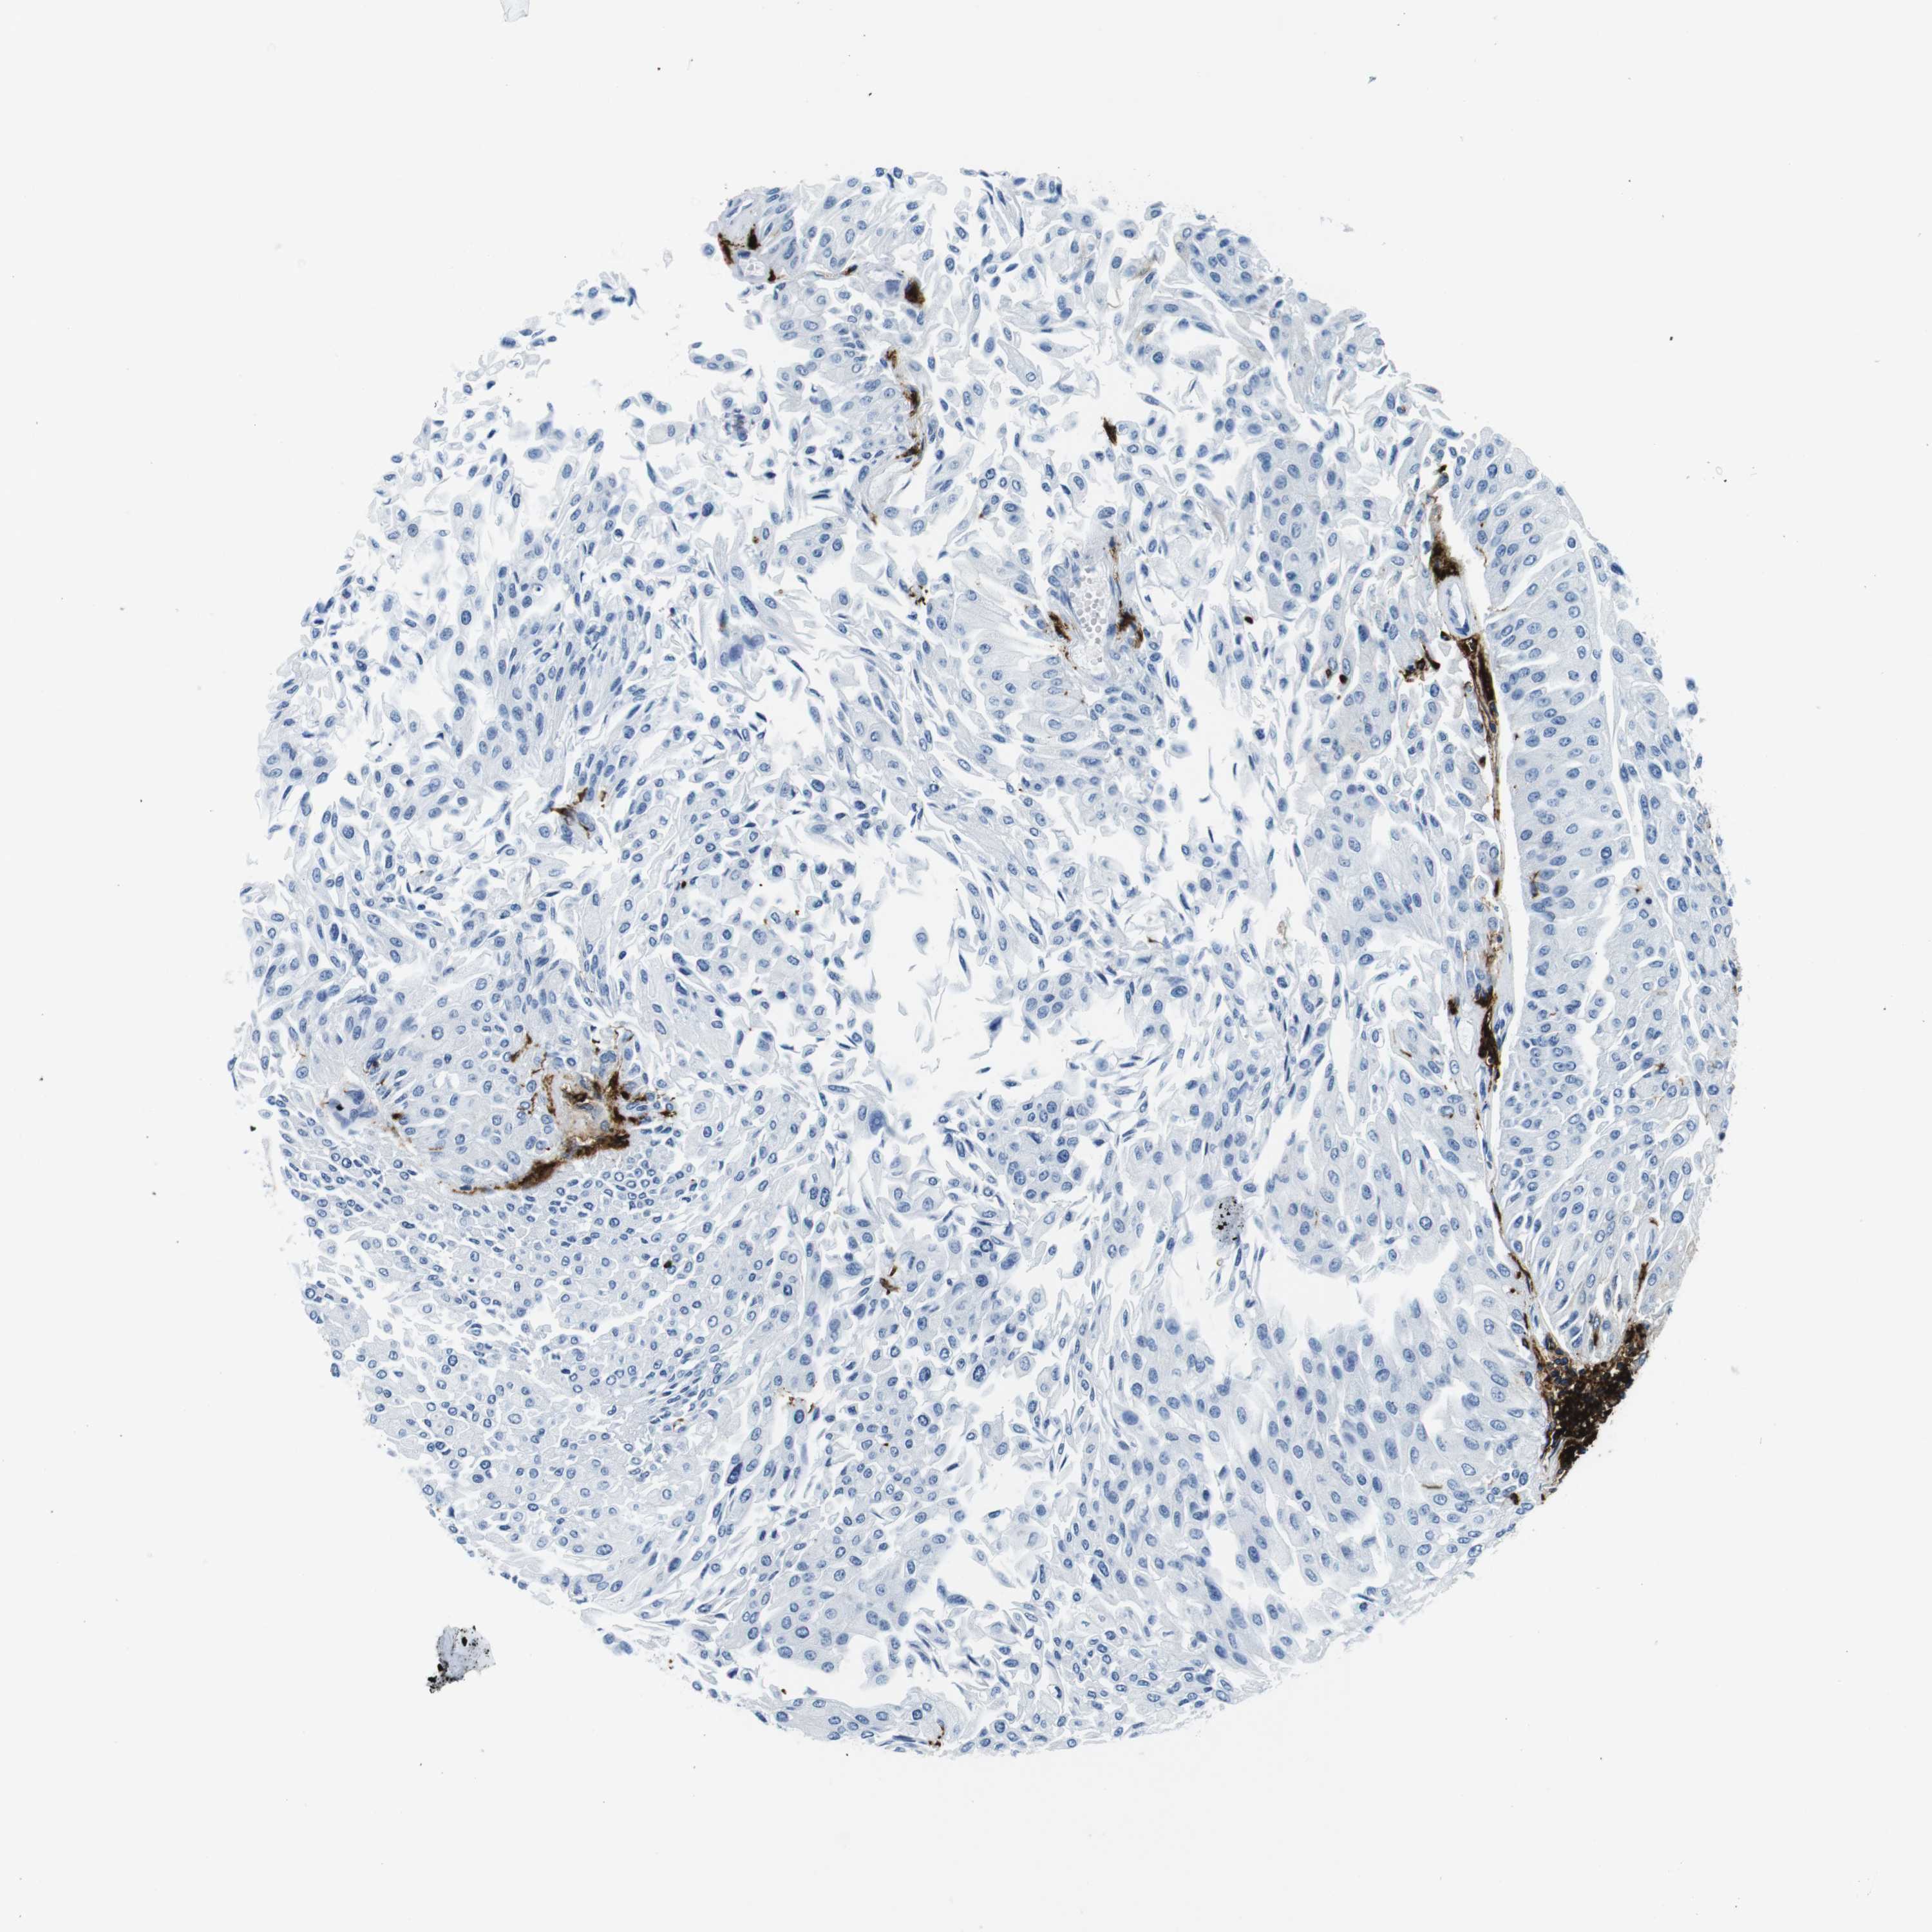

UROTHELIAL CANCER - Protein expressioni

A mouse-over function shows sample information and annotation data. Click on an image to view it in a full screen mode. Samples can be filtered based on level of antibody staining by selecting one or several of the following categories: high, medium, low and not detected. The assay and annotation is described here.

Note that samples used for immunohistochemistry by the Human Protein Atlas do not correspond to samples in the TCGA dataset.

Antibody stainingi

Antibody staining in the annotated cell types in the current human tissue is reported as not detected, low, medium, or high, based on conventional immunohistochemistry profiling in selected tissues. This score is based on the combination of the staining intensity and fraction of stained cells.

Each image is clickable and will lead to virtual microscopy that enables deeper exploration of all samples and also displays staining intensity scores, fraction scores and subcellular localization as well as patient and tissue information for each sample.

Antibody HPA043151

Antibody CAB015400

Antibody CAB034021

Staining

High

Medium

Low

Not detected

Intensity

Strong

Moderate

Weak

Negative

Quantity

>75%

75%-25%

<25%

None

Location

Nuclear

Cytoplasmic/membranous

Cytoplasmic/membranous,nuclear

Urothelial carcinoma, High grade

Urothelial carcinoma, Low grade